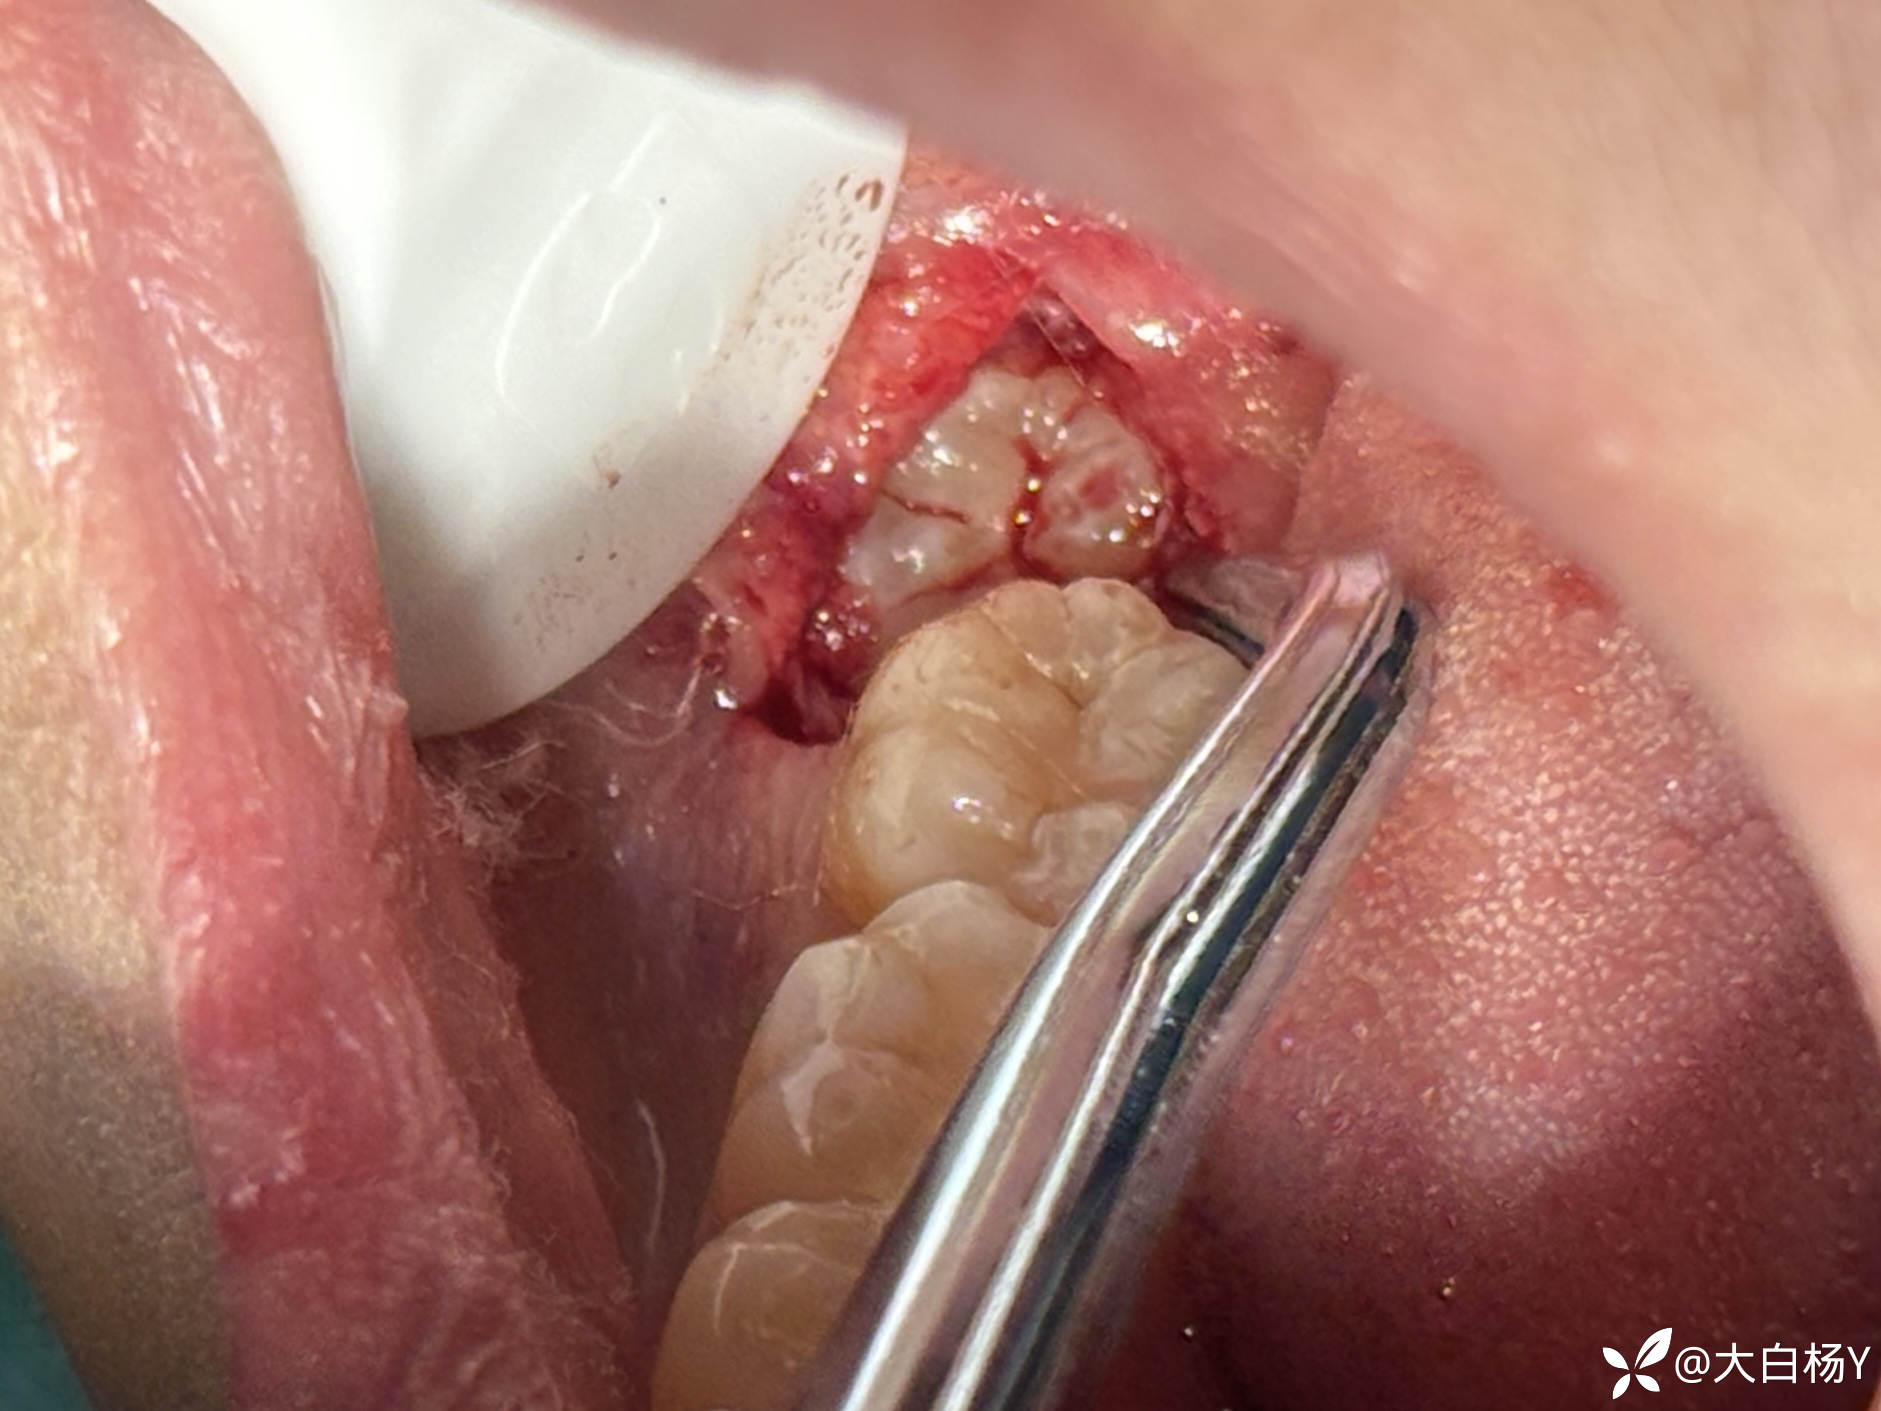

切口:

img